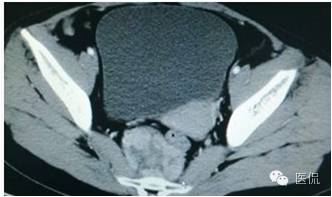

女,37岁,体检超声发现盆腔包块一周。无其他异常。

增强静脉期(CT值62HU)